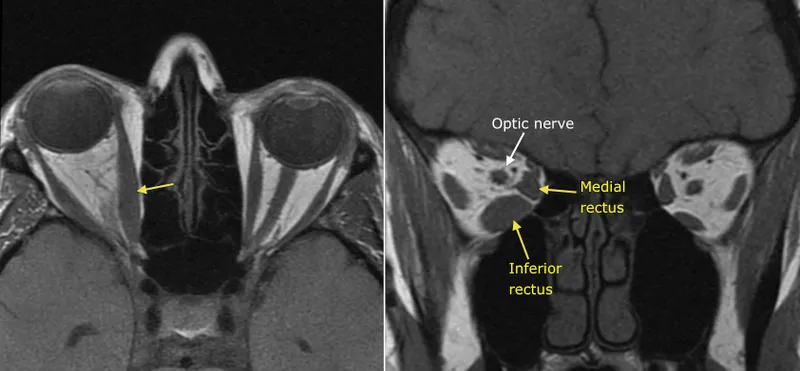

- Thyroid Eye Disease (TED):

- Most common cause of unilateral/bilateral proptosis in adults.

- Diplopia, exposure keratopathy, compressive optic neuropathy.

- CT/MRI: Enlarged extraocular muscles (sparing tendons).

- Mgmt (optic neuropathy): IV methylprednisolone, orbital radiotherapy, surgical decompression.